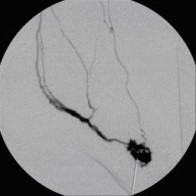

Nach perkutaner transluminaler Angioplastie (PTA) der Unterschenkelgefäße

(Bild 4 von 4)